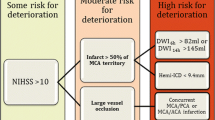

A patient in the fourth decade of life with no significant medical history was found down with global aphasia, right-sided hemiplegia, and homonymous hemianopsia. The patient had been seen normally 36 h prior. Initial non-contrast computed tomography (CT) revealed an established left middle cerebral artery territory infarction (Fig. 1B–C). The left internal carotid (ICA) and middle cerebral arteries (MCA) were occluded, as evidenced by the hyperdense arteries (arrows in Fig. 1A). A CT angiogram revealed an ICA dissection with thrombus propagation into the ipsilateral MCA (image not shown). Over the next 24 h, the patient developed progressive somnolence. A repeat CT head showed an evolving MCA infarct with increasing mass effect over the ipsilateral ventricular system (Fig. 1D–F). The following day, the patient’s level of consciousness further deteriorated, requiring sustained noxious stimulation to achieve eye-opening. A new CT head (Fig. 1G–I) showed increased cerebral edema and worsening mass effect, with a rightward midline shift of 11 mm. This was associated with marked compression of the left lateral ventricle and third ventricle. There were signs of early hydrocephalus with mild enlargement of the right temporal horn (Arrows in Fig. 1G and H). The patient was intubated, received a bolus of 23% hypertonic saline, and was emergently taken to the operating room for decompressive hemicraniectomy with no complications. A postoperative CT head showed appropriate cerebral decompression with a slightly improved midline shift. (Fig. 2A) The next day, the patient’s mental status improved significantly. Seven days later, he was discharged to inpatient rehabilitation, and home 1 month after. On discharge, the patient required assistance for transfers and bodily needs but could stand with help for 40 s (modified Rankin scale [mRS] 4). Severe hemiparesis, aphasia, and right homonymous hemianopia persisted. The patient continued to improve with outpatient rehabilitation and underwent cranioplasty without complications (Fig. 2B). One year after surgery, the patient could walk up to 4 blocks without assistance and communicate with others despite severe expressive aphasia (mRS 2). Unfortunately, the patient developed medically refractory epilepsy with numerous hospitalizations and severe spasticity requiring regular botulinum toxin injections.

Patients with severe hemispheric syndromes from a distal ICA or proximal MCA occlusion who have ischemic changes involving > 50% of the MCA territory on CT within 12 h of symptoms onset are more likely to develop massive hemispheric edema in the following 24 to 72 h [1]. Also, diffusion-weighted magnetic resonance imaging (DWI-MRI) volumes > 80 mL within 6 h [7] and > 145 ml within 14 h of stroke onset predict a malignant evolution [8].

In a meta-analysis of 31 cohort and 7 case-control studies (n = 3278), younger age, higher admission National Institutes of Health Stroke Scale (NIHSS) scores (17–20 for patients with malignant cerebral edema, as compared to 5–15 for those without this complication), and hypoattenuation involving > 50% of the MCA territory on initial CT (OR = 5.33; 95% CI, 2.93–9.68) were associated with the development of malignant cerebral edema [2]. CT hypoattenuation was reliable as early as within 6 h and up to 40 h after symptoms onset. Depressed level of consciousness, gaze palsy, nausea or vomiting, and the need for mechanical ventilation were additional clinical features associated with a higher risk of malignant cerebral edema [2]. Further analysis of brain imaging revealed that more proximal arterial occlusions (OR, 4.89; 95% CI, 2.77–8.64), longer extension of the occlusion (OR, 3.78; 95% CI, 1.96–7.28), and tandem occlusions (OR = 4.05; 95% CI, 2.24–7.34) are additional risk factors [2]. On the other hand, arterial revascularization (OR = 0.37; 95% CI, 0.24–0.57) and brain atrophy were associated with a lower risk of malignant edema. Although age-related brain atrophy possibly mediates the protective effect of age on the development of brain edema, the exact age cutoff for protection and whether age is an independent protective factor for malignant edema deserve further research [2].

Scoring systems

Most available prediction models for malignant MCA stroke are limited by their retrospective design, small sample sizes, and lack of external validation [9,10,11,12,13] (Table 1). The DASH score, for example, requires MRI and quantification of collateral flow, information that may not be widely available [13]. The INTEP-AR score was developed in a multicenter prospective study and addressed most of these limitations [3•]. Among 2183 patients with CT within 24 h, 232 (10.6%) developed malignant brain edema. In the derivation cohort (n = 1627, 11.7% developed malignant edema), higher NIHSS (OR = 1.09, 1.06–1.12), large infarct defined as ≥ 50% of the territory of MCA, anterior cerebral artery (ACA) or posterior cerebral artery (PCA) (OR = 40.90, 95% CI 20.20–82.80), pneumonia (OR = 2.47, 1.53–3.97), intravenous thrombolysis (OR 2.11, 1.18–3.78), and endovascular treatment (OR = 2.87, 1.47–5.59) were associated with the development of malignant MCA infarcts. Brain atrophy (OR = 0.57, 0.37–0.86) and arterial recanalization (OR = 0.36, 0.17–0.75) were associated with a reduced risk [3•]. The score was built with these variables ranging from − 1 to 20, and a score ≥ 10 had good discrimination and calibration for malignant MCA infarct in the derivation (n = 1627, 11,6% had malignant edema, AUC 0.89, 0.87–0.92; sensitivity 0.95, 0.92–0.98) and validation (n = 556 patients, 7.7% had malignant brain edema, AUC 0.88, 0.82–0.95; sensitivity 0.84, 0.73–0.95) cohorts [3•]. The analysis of estimates for each variable indicates that stroke size is the single most important variable associated with increased risk for the development of malignant edema.